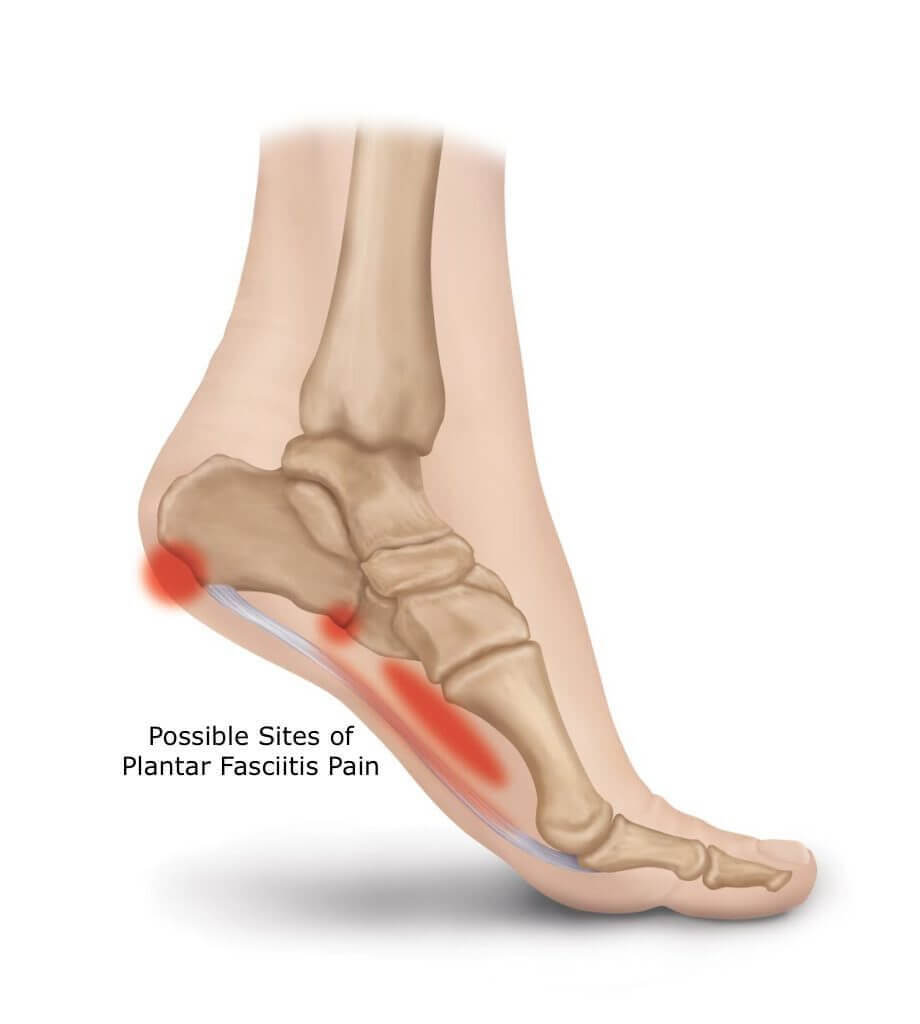

Heel Pain Causes Treatment and Prevention top, Do You Wake Up In The Morning With Excruciating Pain In Your Heels Sutherland Podiatry top, Causes of Morning Heel Pain in Arizona Fixing Feet PLLC top, Why Do I Have Heel Pain in the Morning SPORT Orthopedics top, Why Do I Have Heel Pain in the Morning Here s How to Relieve the Pain Feet Feet top, 5 Reasons You May be Experiencing Foot Pain in the Morning Foot and Ankle Group top, Why do my feet hurt when I wake up and walk top, Foot Pain In The Morning Causes Treatment top, Why Do My Heels Hurt in the Morning Northeast Foot and Ankle top, Heel Pain After Waking Up in the Morning Dr. Chetan Oswal Pune top, Early morning heel pain causes remedies prevention top, Heel Pain in the Morning Here s What It May Mean Advanced Foot Ankle Center Podiatry top, Heel Pain Plantar Fasciitis is a common and Painful Condition top, Heel Pain Causes Diagnosis Treatment top, Why Pain From Plantar Fasciitis Is Worse in the Morning top, Why does my heel hurt when I get up in the morning Catching Health with Diane Atwood top, The Consequences of Leaving Plantar Fasciitis Untreated Plantar Fasciitis top, It Hurts to Put Pressure on My Feet in the Mornings Premier Podiatry top, Plantar Fasciitis Orthopaedic Foot Ankle Surgeon Edinburgh Mr. H Shalaby top, Causes of Morning Heel Pain Blog top, The Do s and Don ts of Plantar Fasciitis Lucky Feet Shoes top, Pioneer Podiatry top, Why Plantar Fasciitis Feels Worse in the Morning Washington Foot Ankle Sports Medicine Podiatry top, How to Treat Your Morning Heel Pain at Home in 3 Easy Steps Foot Leg Centre top, Plantar Fasciitis Causes Symptoms Treatments and More top, Plantar fasciitis Plantar fasciitis is caused by aseptic inflammation of the plantar tendons or fascia. The most common symptoms are heel pain and discomfort often at the heel of the foot sometimes top, Heel pain or plantar fasciitis Treatment exercises and causes top, 4 Heel Pain Symptoms to Take Seriously Chicagoland Foot and Ankle Board Certified Foot and Ankle Specialists and Surgeons top, Plantar fasciitis Symptoms and causes Mayo Clinic top, What is Plantar Fasciitis Common Causes of Plantar Fasciitis top, Common Causes of Heel Pain top, Plantar Fasciitis and Bone Spurs OrthoInfo AAOS top, Plantar Fasciitis Symptoms and Treatment familydoctor top, 2 Major Causes of Heel Pain Leading Edge Physiotherapy St Albert Edmonton Physical Therapy top, Why Heel Pain Won t Disappear Foot and Ankle Podiatrists top.

Heel pain worse in morning top